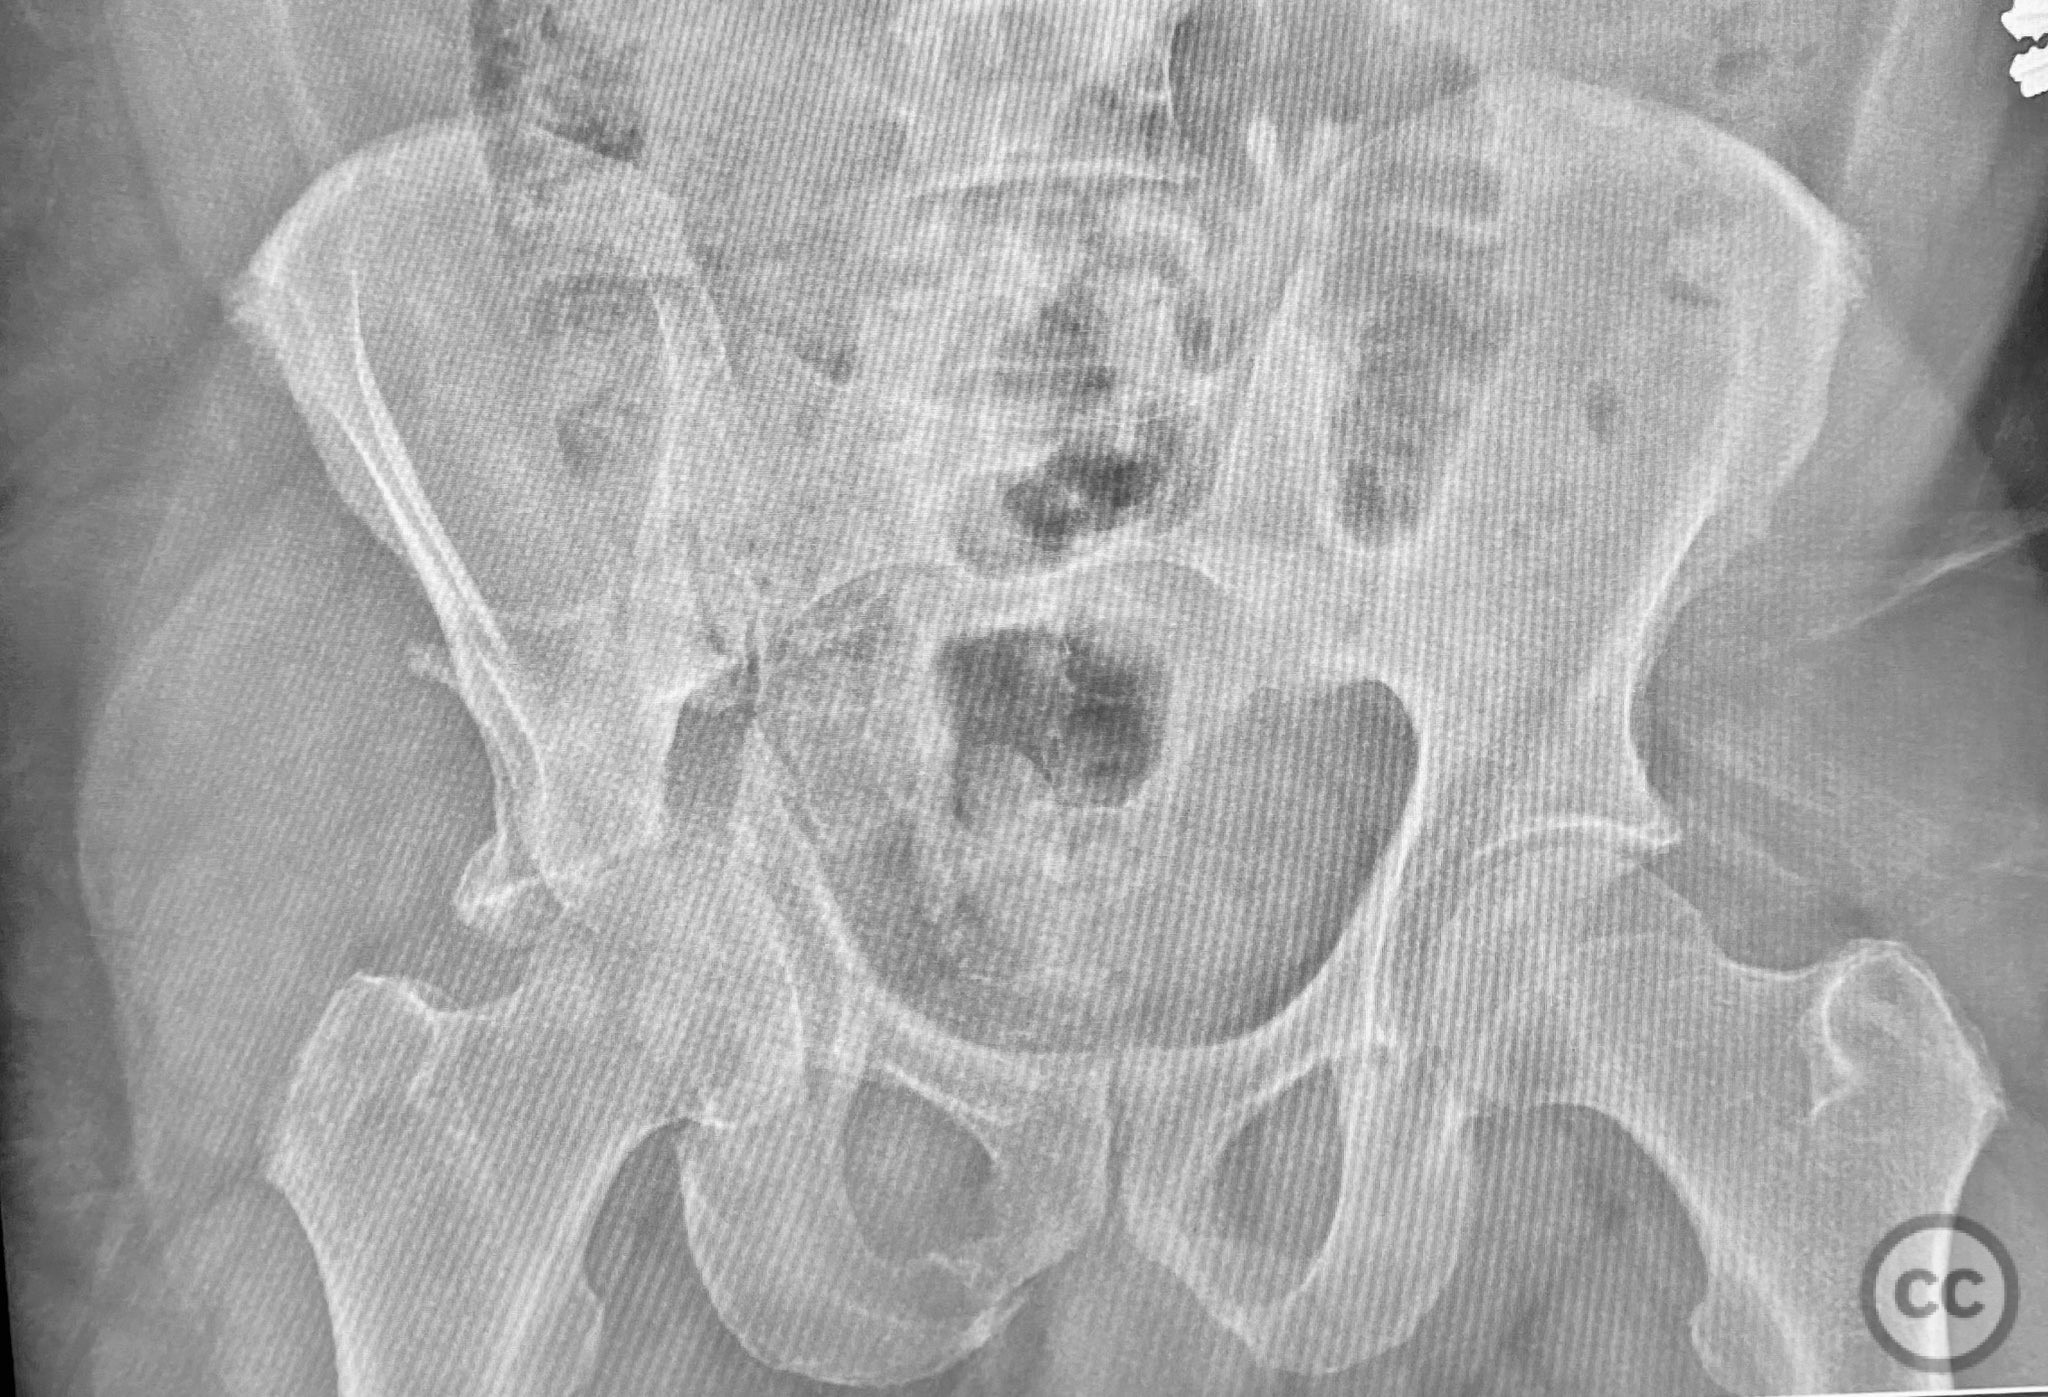

Uploaded on Sep 12 2025

Posterior Wall Acetabular Fracture-Dislocation w...

• Case by Chip Routt

Specialist Consultant - United States